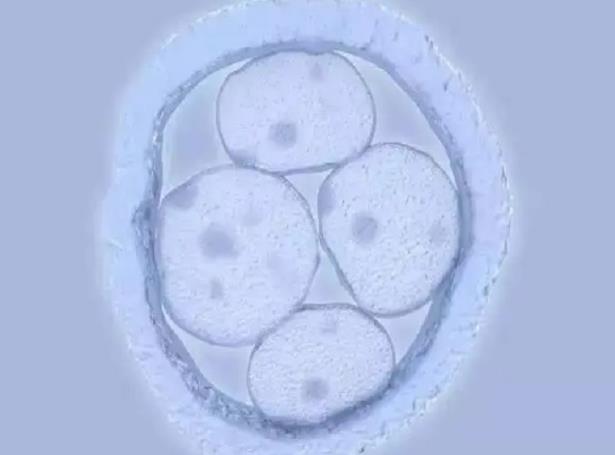

2、胚胎質量:不好的胚胎不容易成功,優質的胚胎容易成功。一個好的胚胎與男女雙方的精子和卵子質量密切相關。